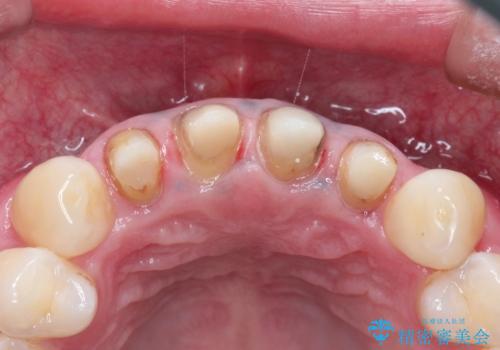

- 上の前歯の見た目が気になるとのことで来院されました。

上の前歯の4本が神経の処置がされており、前から2番目の歯が内側に入り込んでしまっていました。

また、金属で治療された根本の歯茎が黒く変色(メタルタトゥー)しており、余計に見た目がよくない状態となっておりました。